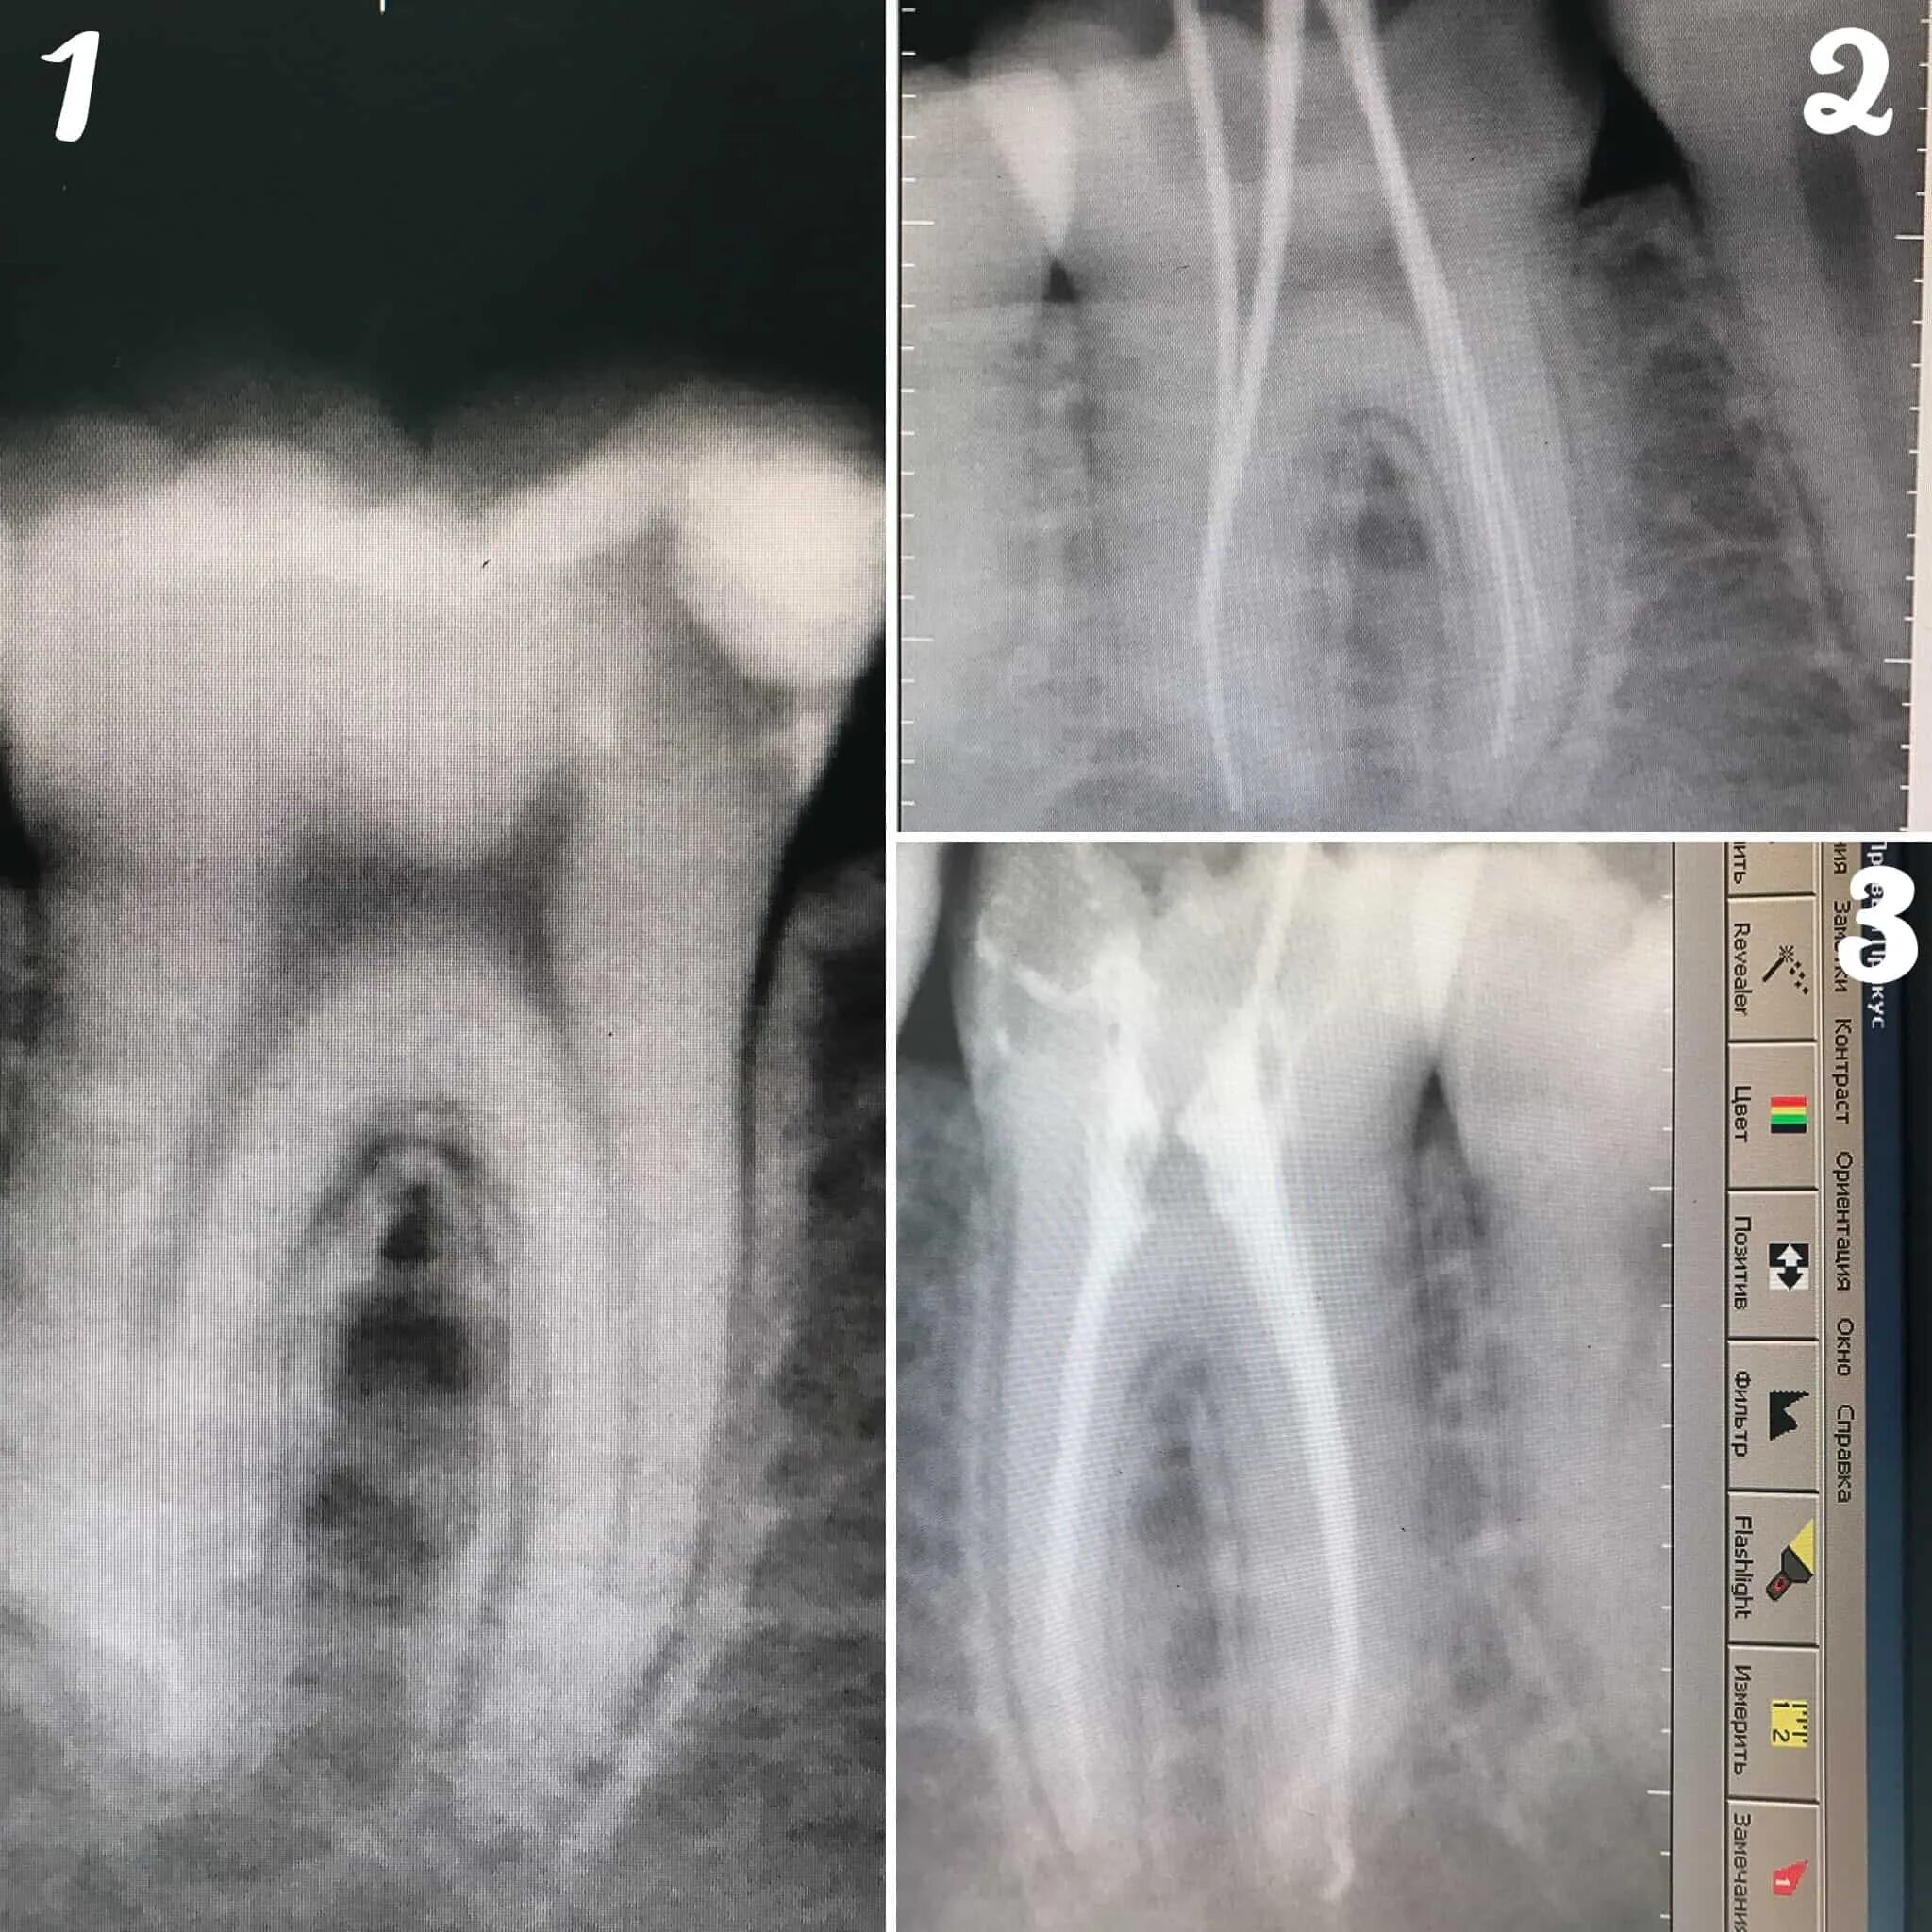

Как вылечить пульпит